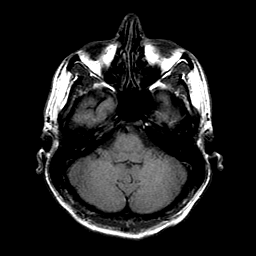

Sarcoma, MR Study #1 mr-t1 -- Slice #4

[Home][Help][Clinical] Slice 4